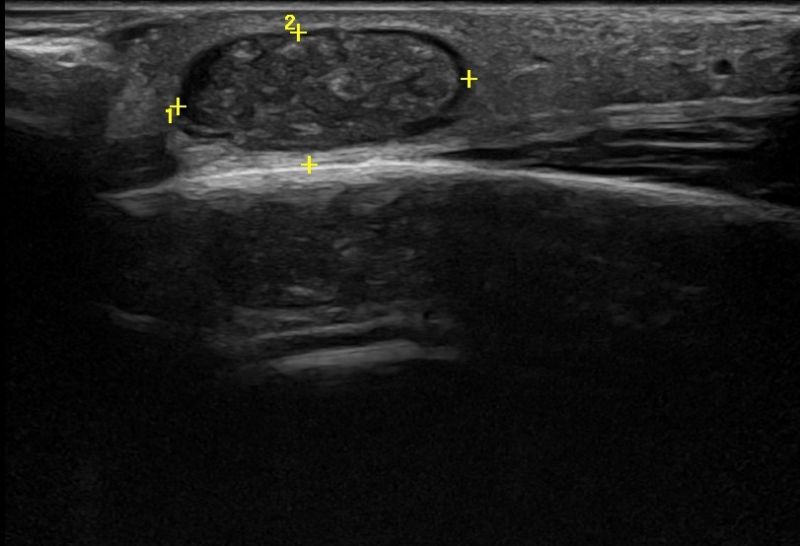

Η τεχνική του Έγχρωμου Doppler μελετάει την αγγείωση της βλάβης. Η τεχνική του Παλμικού Doppler μελετάει την παρουσία αρτηριακών ή φλεβικών στοιχείων εντός της βλάβης. Επίσης πολύ χρήσιμη είναι η Ελαστογραφική Μελέτη η οποία μελετάει τη σκληρότητας της βλάβης. Οι τεχνικές αυτές μας βοηθούν να χαρακτηρίσουμε αν η βλάβη είναι αγγειακού τύπου και αν έχει καλοήθη η ύποπτα χαρακτηριστικά.

Η εξέταση δεν απαιτεί κάποια ιδιαίτερη προετοιμασία. Ο εξεταζόμενος, ανάλογα με την περιοχή του ευρήματος, εξετάζεται ξαπλωμένος ή καθιστός μετά από την τοποθέτηση ζελέ στην περιοχή. Με τη χρήση ειδικών ηχοβόλων κεφάλων υψηλής ευκρίνειας γίνεται η εξέταση. Εκτός από την ασπρόμαυρη εξέταση (B- mode) γίνεται μελέτη με έγχρωμο Power Doppler και Ελαστογραφία. Η διάρκεια της εξέτασης είναι 20-30 λεπτά.